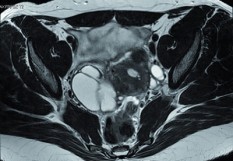

En cette journée internationale de lutte pour les droits des femmes, la ministre de la Santé a participé à une table-ronde réunissant associations de patientes et collèges de professionnels de santé pour "aborder les difficultés actuellement rencontrées par les femmes atteintes d'endométriose", indique un communiqué diffusé à l'issue de ce déplacement. L'endométriose est une maladie "encore trop souvent méconnue du grand public, des femmes et des professionnels de santé", constate le ministère, pointant le manque d'information et les lacunes de la formation des soignants, qui aboutissent parfois à "des parcours de soins chaotiques". La table-ronde a également été l'occasion d'évoquer les voies d'amélioration et les pistes de recherche. Au terme de sa visite au centre de l'endométriose du groupement hospitalier Paris-Saint-Joseph (Paris 14e), Agnès Buzyn a annoncé un plan d'actions en trois axes.

Le premier vise à "détecter précocement l'endométriose", afin de réduire l'errance diagnostique. Les nouvelles consultations obligatoires du calendrier de suivi médical de l'enfant et de l'adolescent, à 11-13 ans et 15-16 ans pour les jeunes filles, doivent être l'occasion de rechercher les signes d'endométriose. Tout comme les consultations dédiées à la santé sexuelle des jeunes filles entre 15 et 18 ans. Il faut aussi "mobiliser les services universitaires de médecine préventive et de promotion de la santé". Pour cela, un renforcement de la formation initiale et continue des professionnels de santé sur les signes d'alerte, le diagnostic et la prise en charge de premier recours de l'endométriose est nécessaire.

Le deuxième axe doit permettre de mieux accompagner les femmes et rendre simples et cohérents les parcours de soins. Pour éviter les parcours de soins "erratiques", "chaque région doit identifier sa 'filière endométriose'" regroupant l'ensemble des professionnels de ville et de l'hôpital ainsi que les associations de patientes ayant l'expertise de cette pathologie, d'ici la fin de l'année 2019. Un groupe de travail national sera mis en place. "La prise en charge de la douleur et des troubles de la fertilité devront faire l’objet d’une vigilance particulière dans ces parcours", insiste le ministère dans son communiqué. Le troisième axe est centré sur l'amélioration des campagnes de communication. Le ministère entend pour cela mobiliser le service sanitaire des étudiants en santé, "dans le cadre des interventions sur la santé sexuelle, pour informer les élèves dans les collèges et les lycées sur la maladie et sensibiliser les futurs professionnels de santé". Enfin, l'endométriose doit faire l'objet d'un "champ de recherche à part entière".